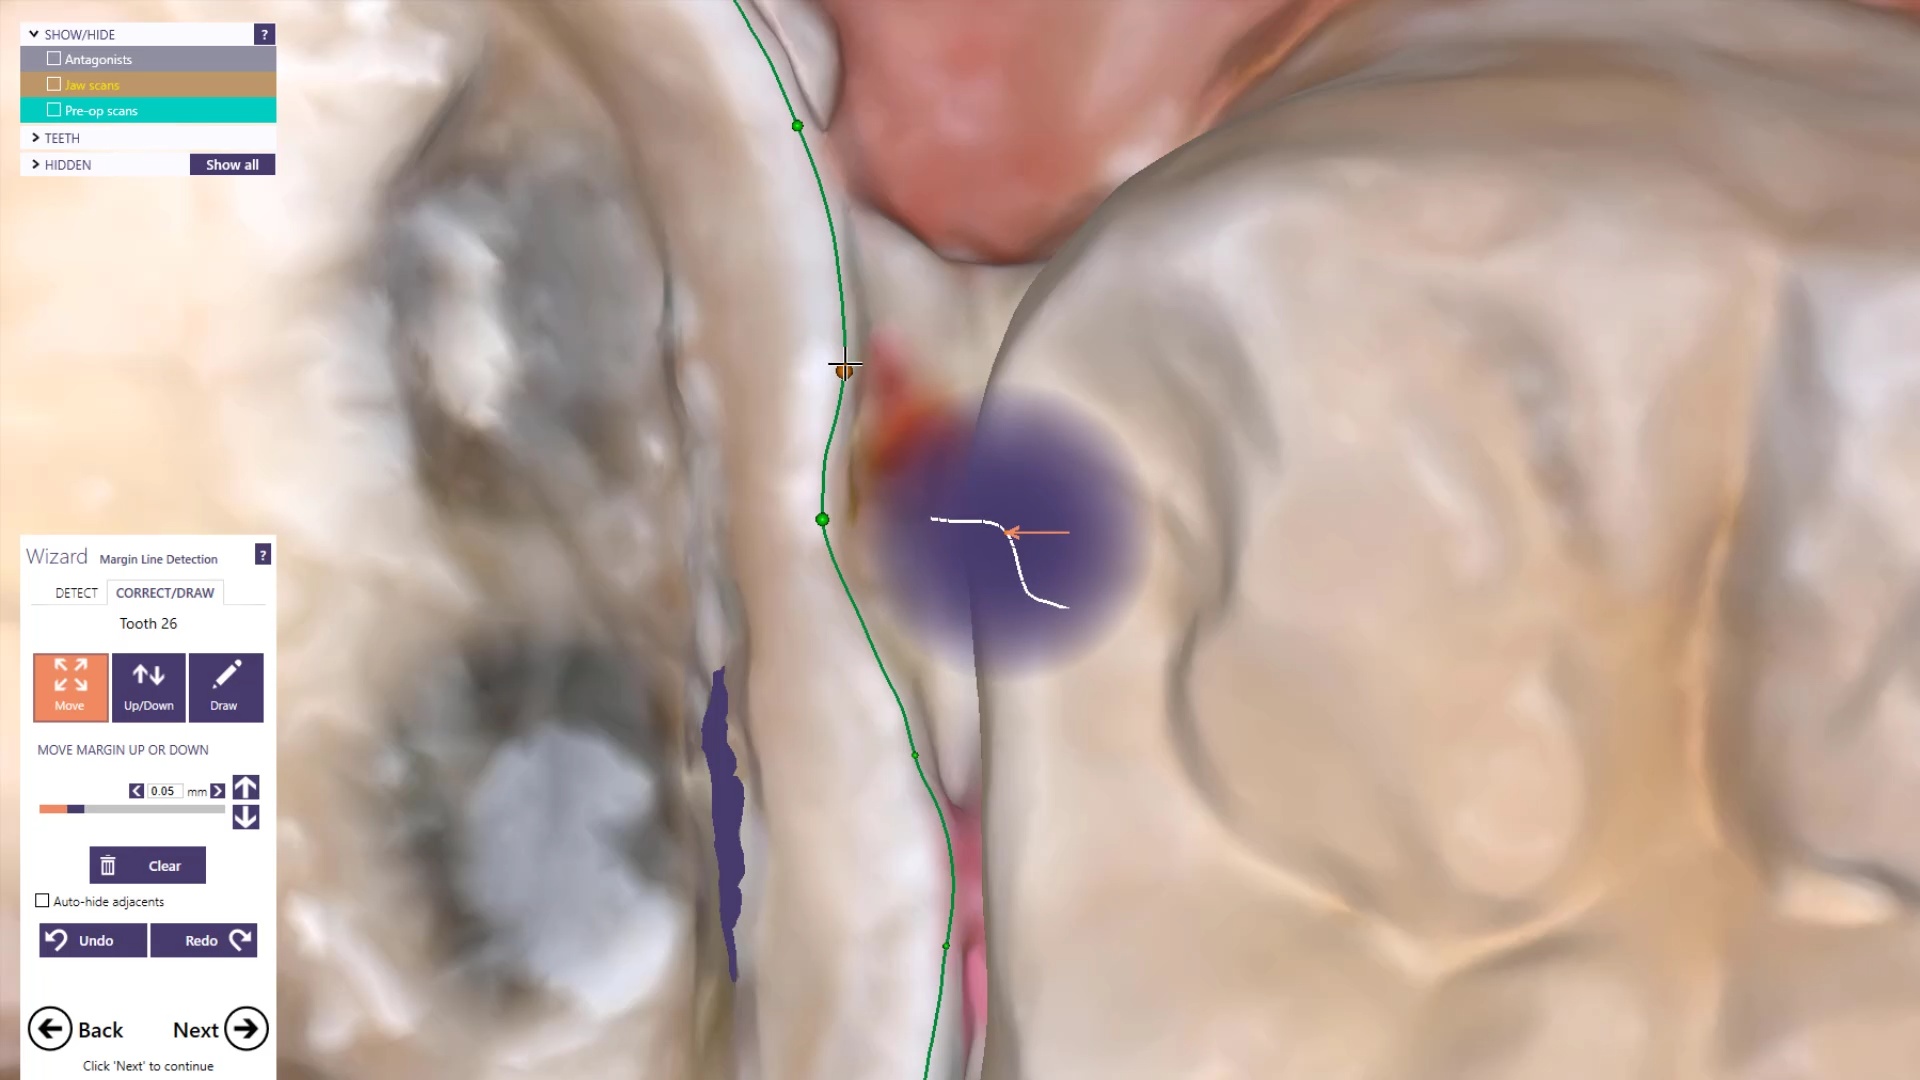

A Medit i500 scan was taken and merged with a CT scan and the distance to bone was measured (5.5 mm’s) giving enough space for soft tissue contouring with […]